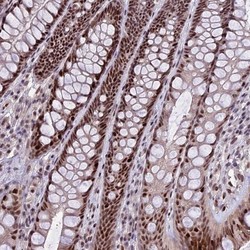

Supportive validation

- Submitted by

- Novus Biologicals (provider)

- Main image

- Experimental details

- Immunohistochemistry-Paraffin: TCP11L2 Antibody [NBP1-82694] - Staining of human rectum shows strong nuclear positivity in glandular cells.